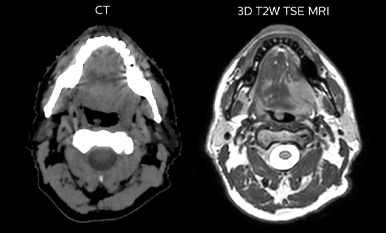

Epidermoid carcinoma of the left tongue base

The patient was diagnosed with an epidermoid carcinoma of the base of the left invading the amygdala lodge and the amygdaloglossal groove. Radiochemotherapy with curative aim was prescribed with a dose of 70 Gy for the tumor, 66 Gy on the suspicious nodes and 56 Gy on the elective drainage areas - in 33 fractions.

T2W 3D, 3D STIR and mDIXON MRI scans.

Comparison of CT simulation scan (left) and T2W 3D MRI (right)

MR-based target contouring on 3D T2W TSE in transversal, sagittal and coronal planes.